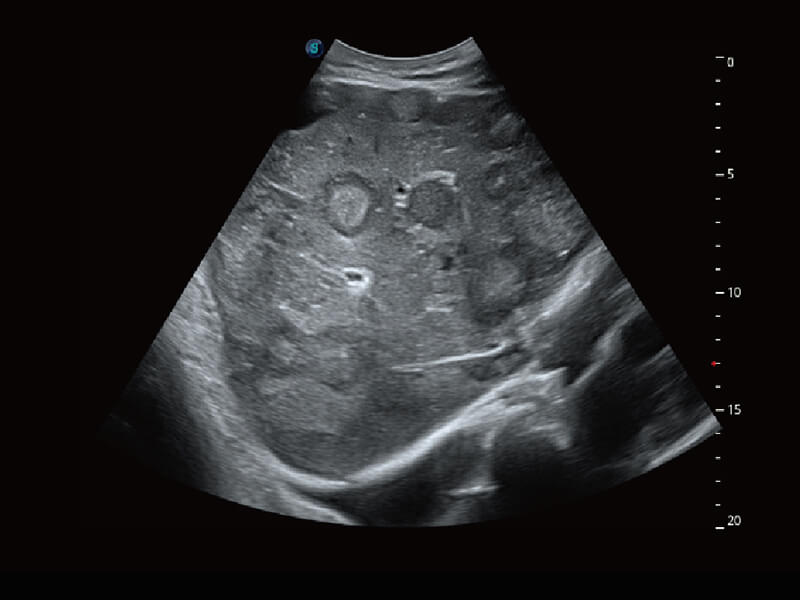

S60探头工艺,从前端信号处理每一个环节采集无损声学数据,真实还原组织原貌,再现解剖细节。

临床图